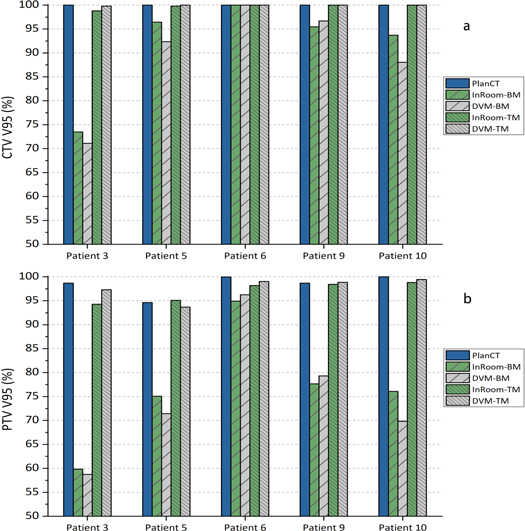

3.3. Results of large inter-fractional motions

The CTV and PTV coverage comparisons of five patients simulating large inter-fractional motions are shown in figure 8 and table 1. CTV coverage differences between InRoom-BM and DVM-BM and between InRoom-TM and DVM-TM were 2.18 ± 2.82% and −0.24 ± 0.42%, respectively. PTV coverage differences between InRoom-BM and DVM-BM and between InRoom-TM and DVM-TM were 1.59 ± 3.36% and −0.7 ± 1.6%, respectively. The dose coverage differences between in-room CTs and DVM CTs were small in both BM and TM scenarios. The magnitude of the change in dose coverage of the DVM CT followed that of the in-room CT at different isocenters in all selected patients. This indicated that in-room CTs and DVM CTs had high similarities in dose distribution, and the DVM technique could be applied to patient data with relatively large inter-fractional motions. The dose coverage differences between InRoom-TM and DVM-TM were slightly smaller than those between the InRoom-BM and DVM-BM. A possible reason for this is that the proportion of the CTV/PTV located on the steep dose gradient region was higher for BM than TM, making the dose coverage sensitive to small displacement differences.

Figure 8. Clinical target volume (CTV; (a)) and planning target volume (PTV; (b)) coverage (V95%) of PlanCT, InRoom-BM, DVM-BM, InRoom-TM, and DVM-TM in five patients with large inter-fractional motions.